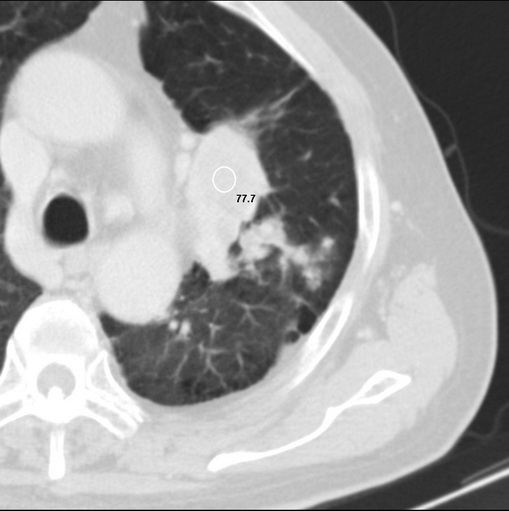

男性患者 81岁 咳嗽 咳痰 咯血

左肺中心型肺癌并:1.左肺阻塞性肺炎;2.纵隔淋巴结肿大;

强化较典型,左上肺癌并纵膈淋巴结转移;左上肺结核并空洞形成;胸膜增厚.

考虑左上肺癌并阻塞性肺炎,左肺转移、左肺门及纵隔淋巴结转移。

肿块贴近左肺门,包绕左上肺动脉,形态不规则。肿块增强扫描中度强化。纵膈内主动脉弓左旁间隙、气管隆突前、下间隙见多枚淋巴结影。综上考虑左侧中央型肺癌可能性大。图片没有完整上传,尤其是左肺上叶支气管分支层面没有上传,因此不好判断是叶支气管中断还是段支气管中断。另外,下图红色部分所示是“黏液支气管征”吗?